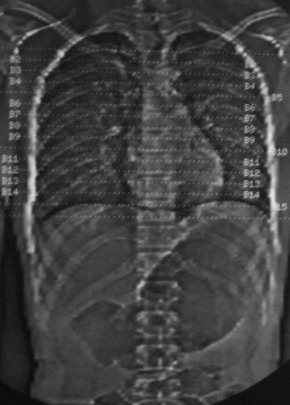

男,18岁,车祸20小时后胸ct.血氧饱和度80,呼吸45次/分.

1:双肺挫裂伤,以双下肺明显。

2:纵隔气肿。

1.双肺挫伤,2.纵隔积气。注意右侧主支气管是否有断裂?